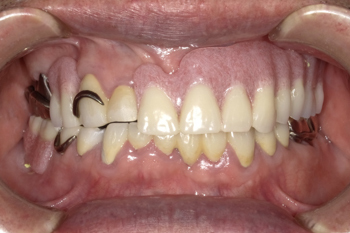

70代男性。修理を繰り返した義歯で噛みにくくなったために金属床義歯治療を行った症例。

治療内容:義歯の人工歯が摩耗していたうえに見た目にも支障があったため、噛み合わせの高さを挙上し、旧義歯に代わって、上下顎金属床義歯を製作しました。

治療期間:約12か月間

リスク・副作用:経年的な顎骨の吸収に対する調整の必要性、義歯を装着している違和感など